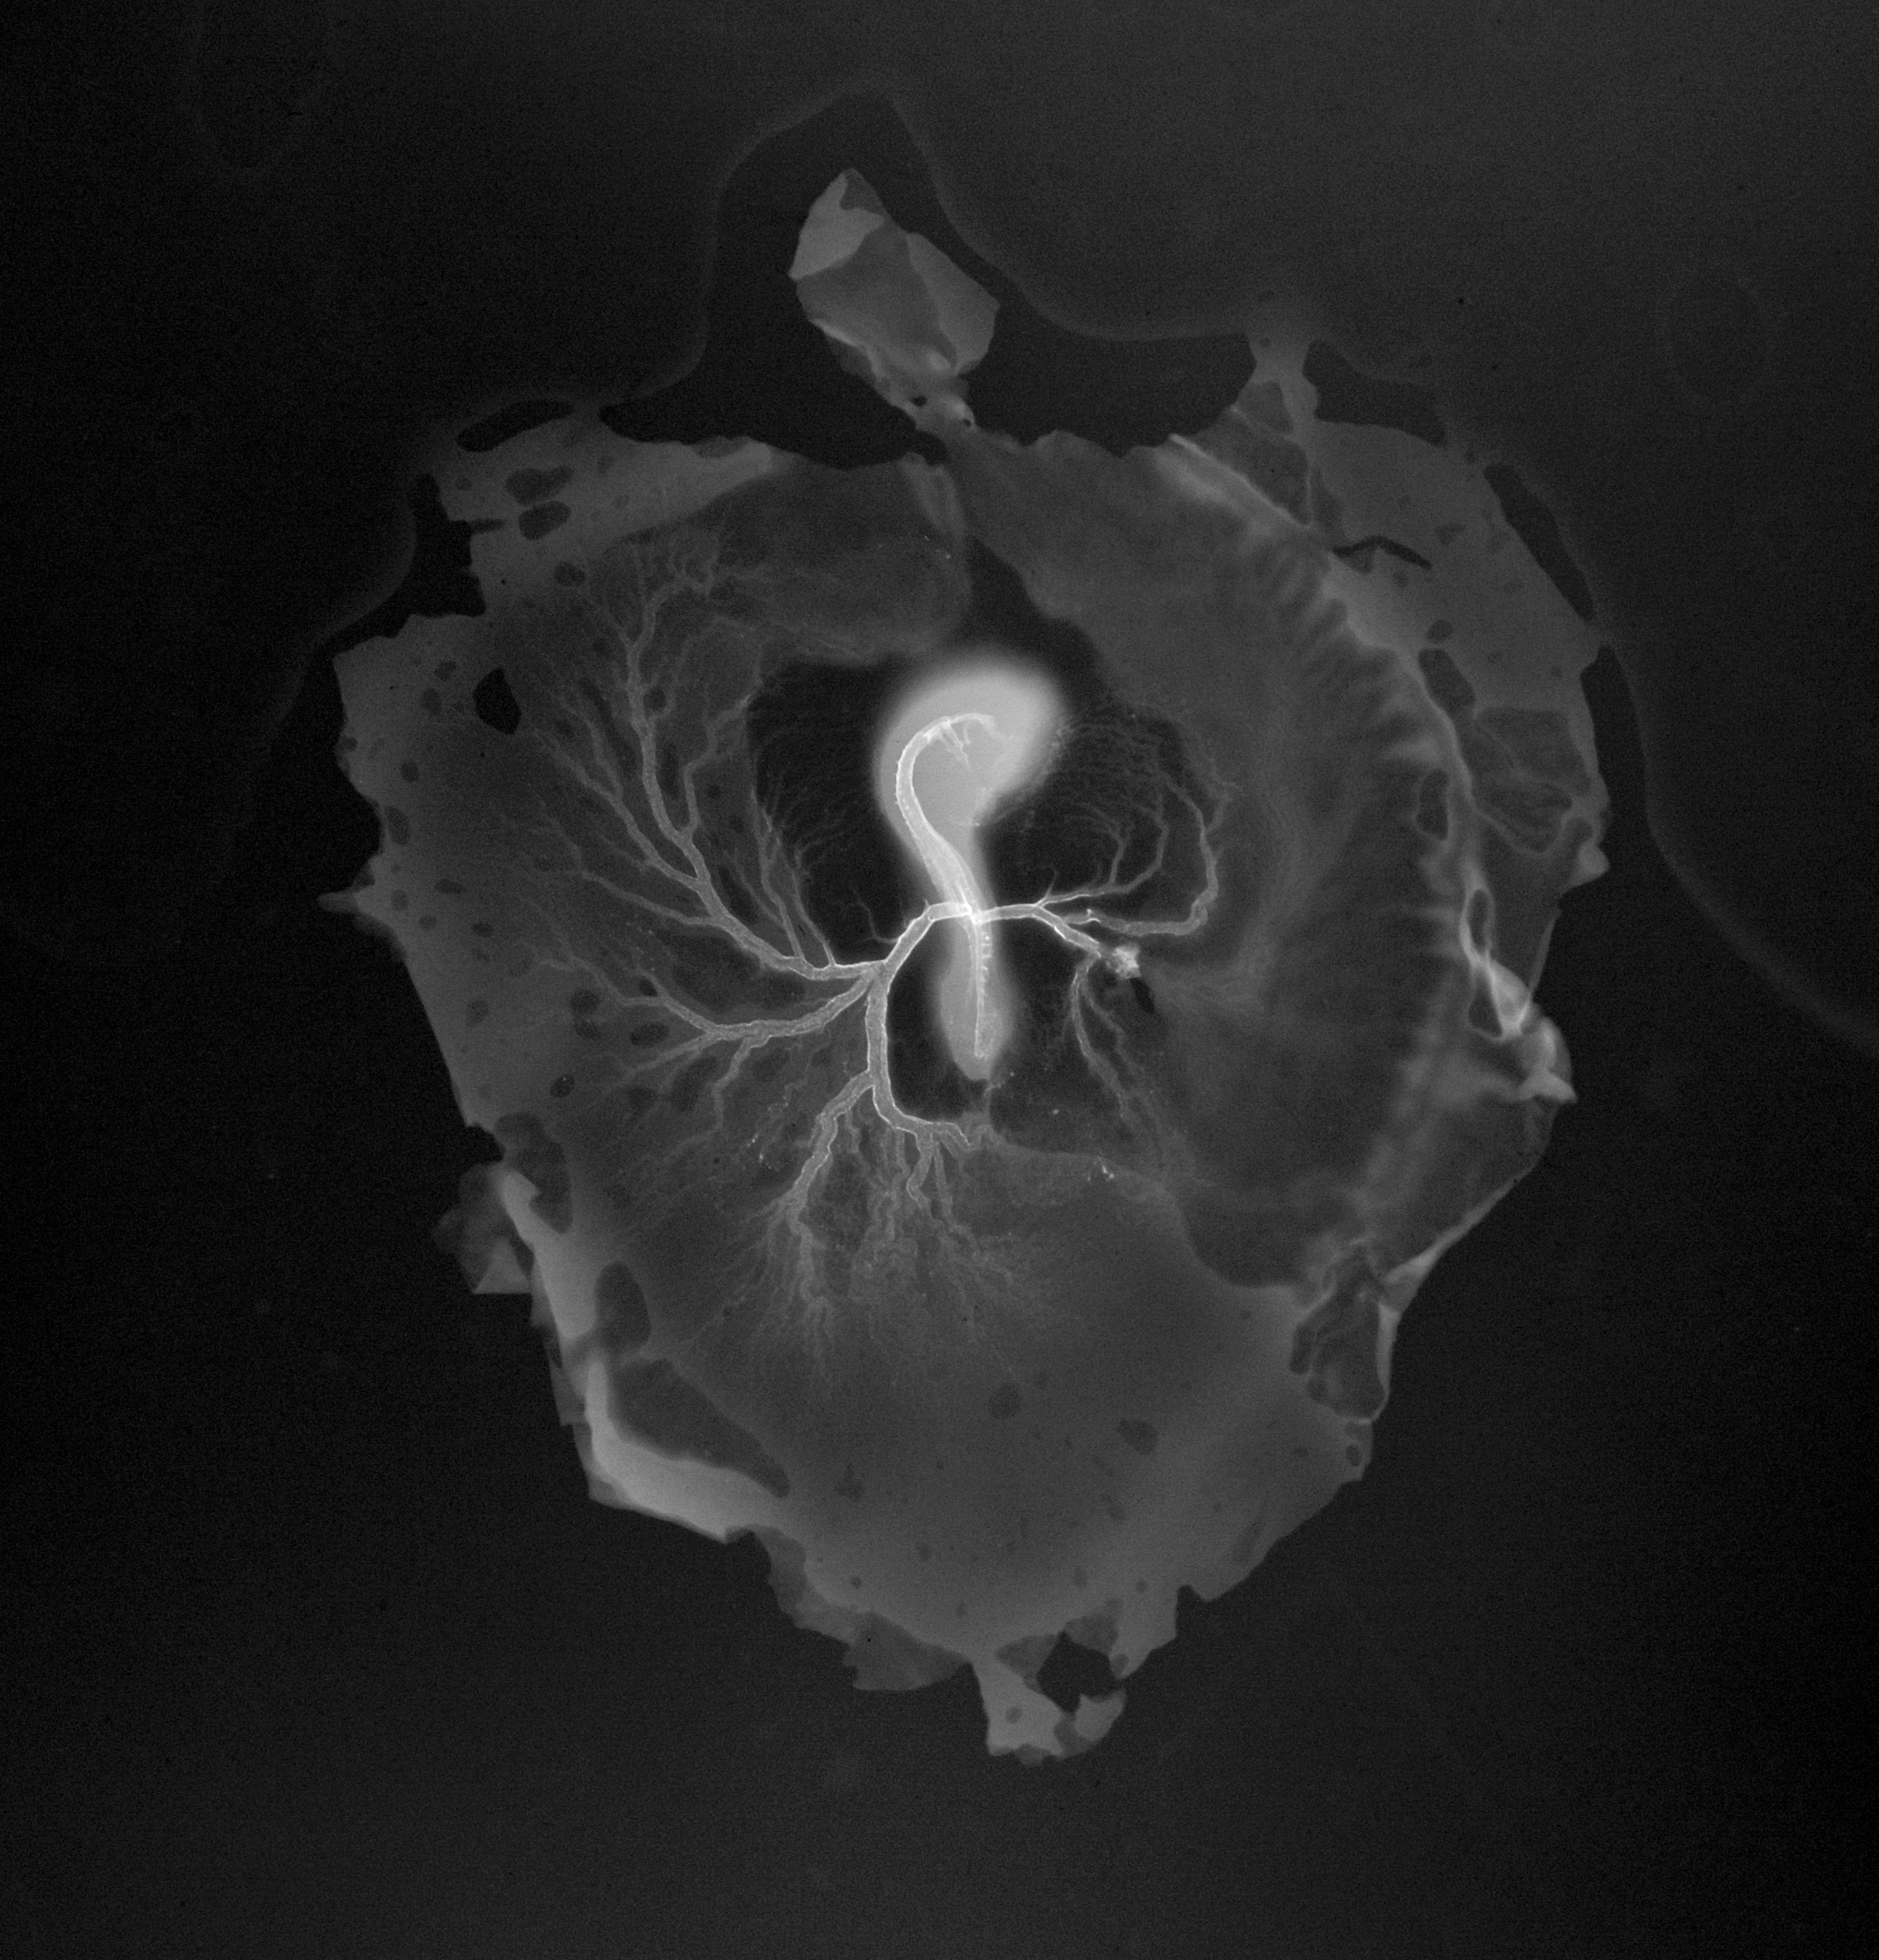

Chick Embryo Microangiography

Hamburger-Hamilton (HH) Stage 16 (approx. 2.1 - 2.5 days)

X-Ray Micrographs